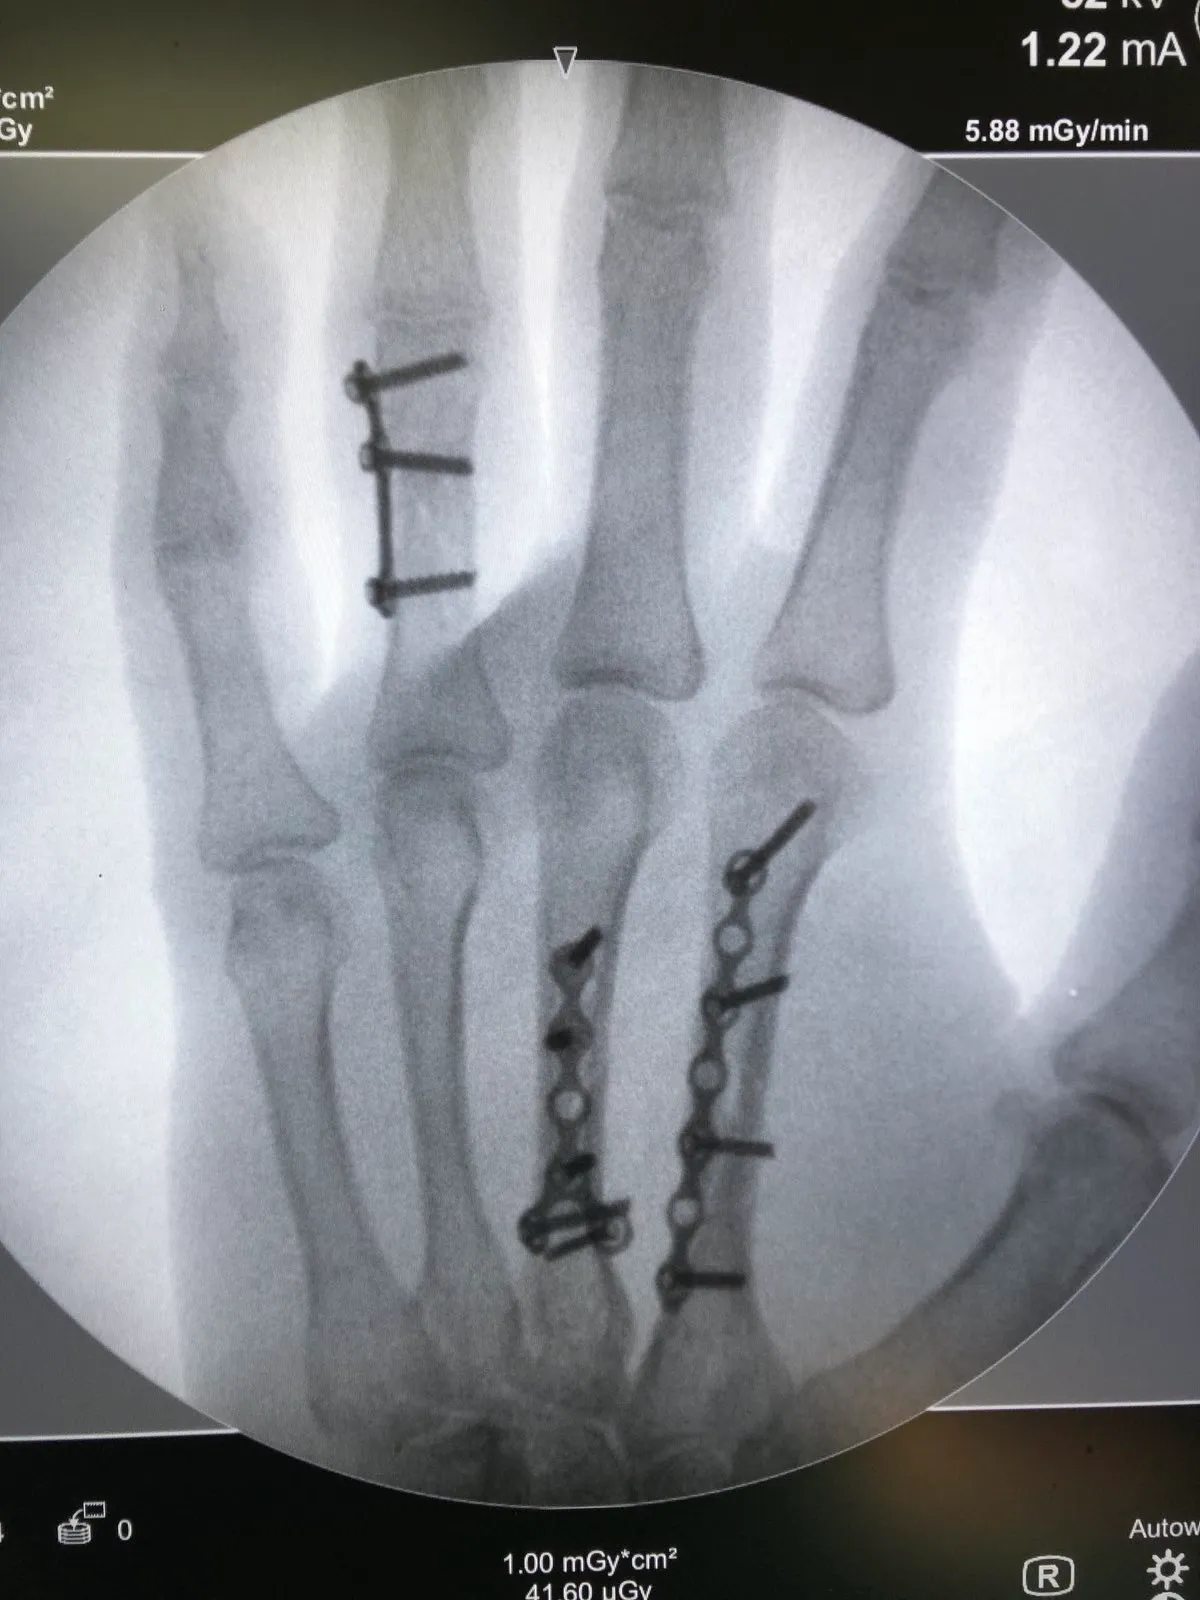

• Лечение переломов костей кисти и верхней конечности любой степени сложности и их последствий

• Репозиция и фиксация переломов (костей запястья, пястных костей, фаланг пальцев)